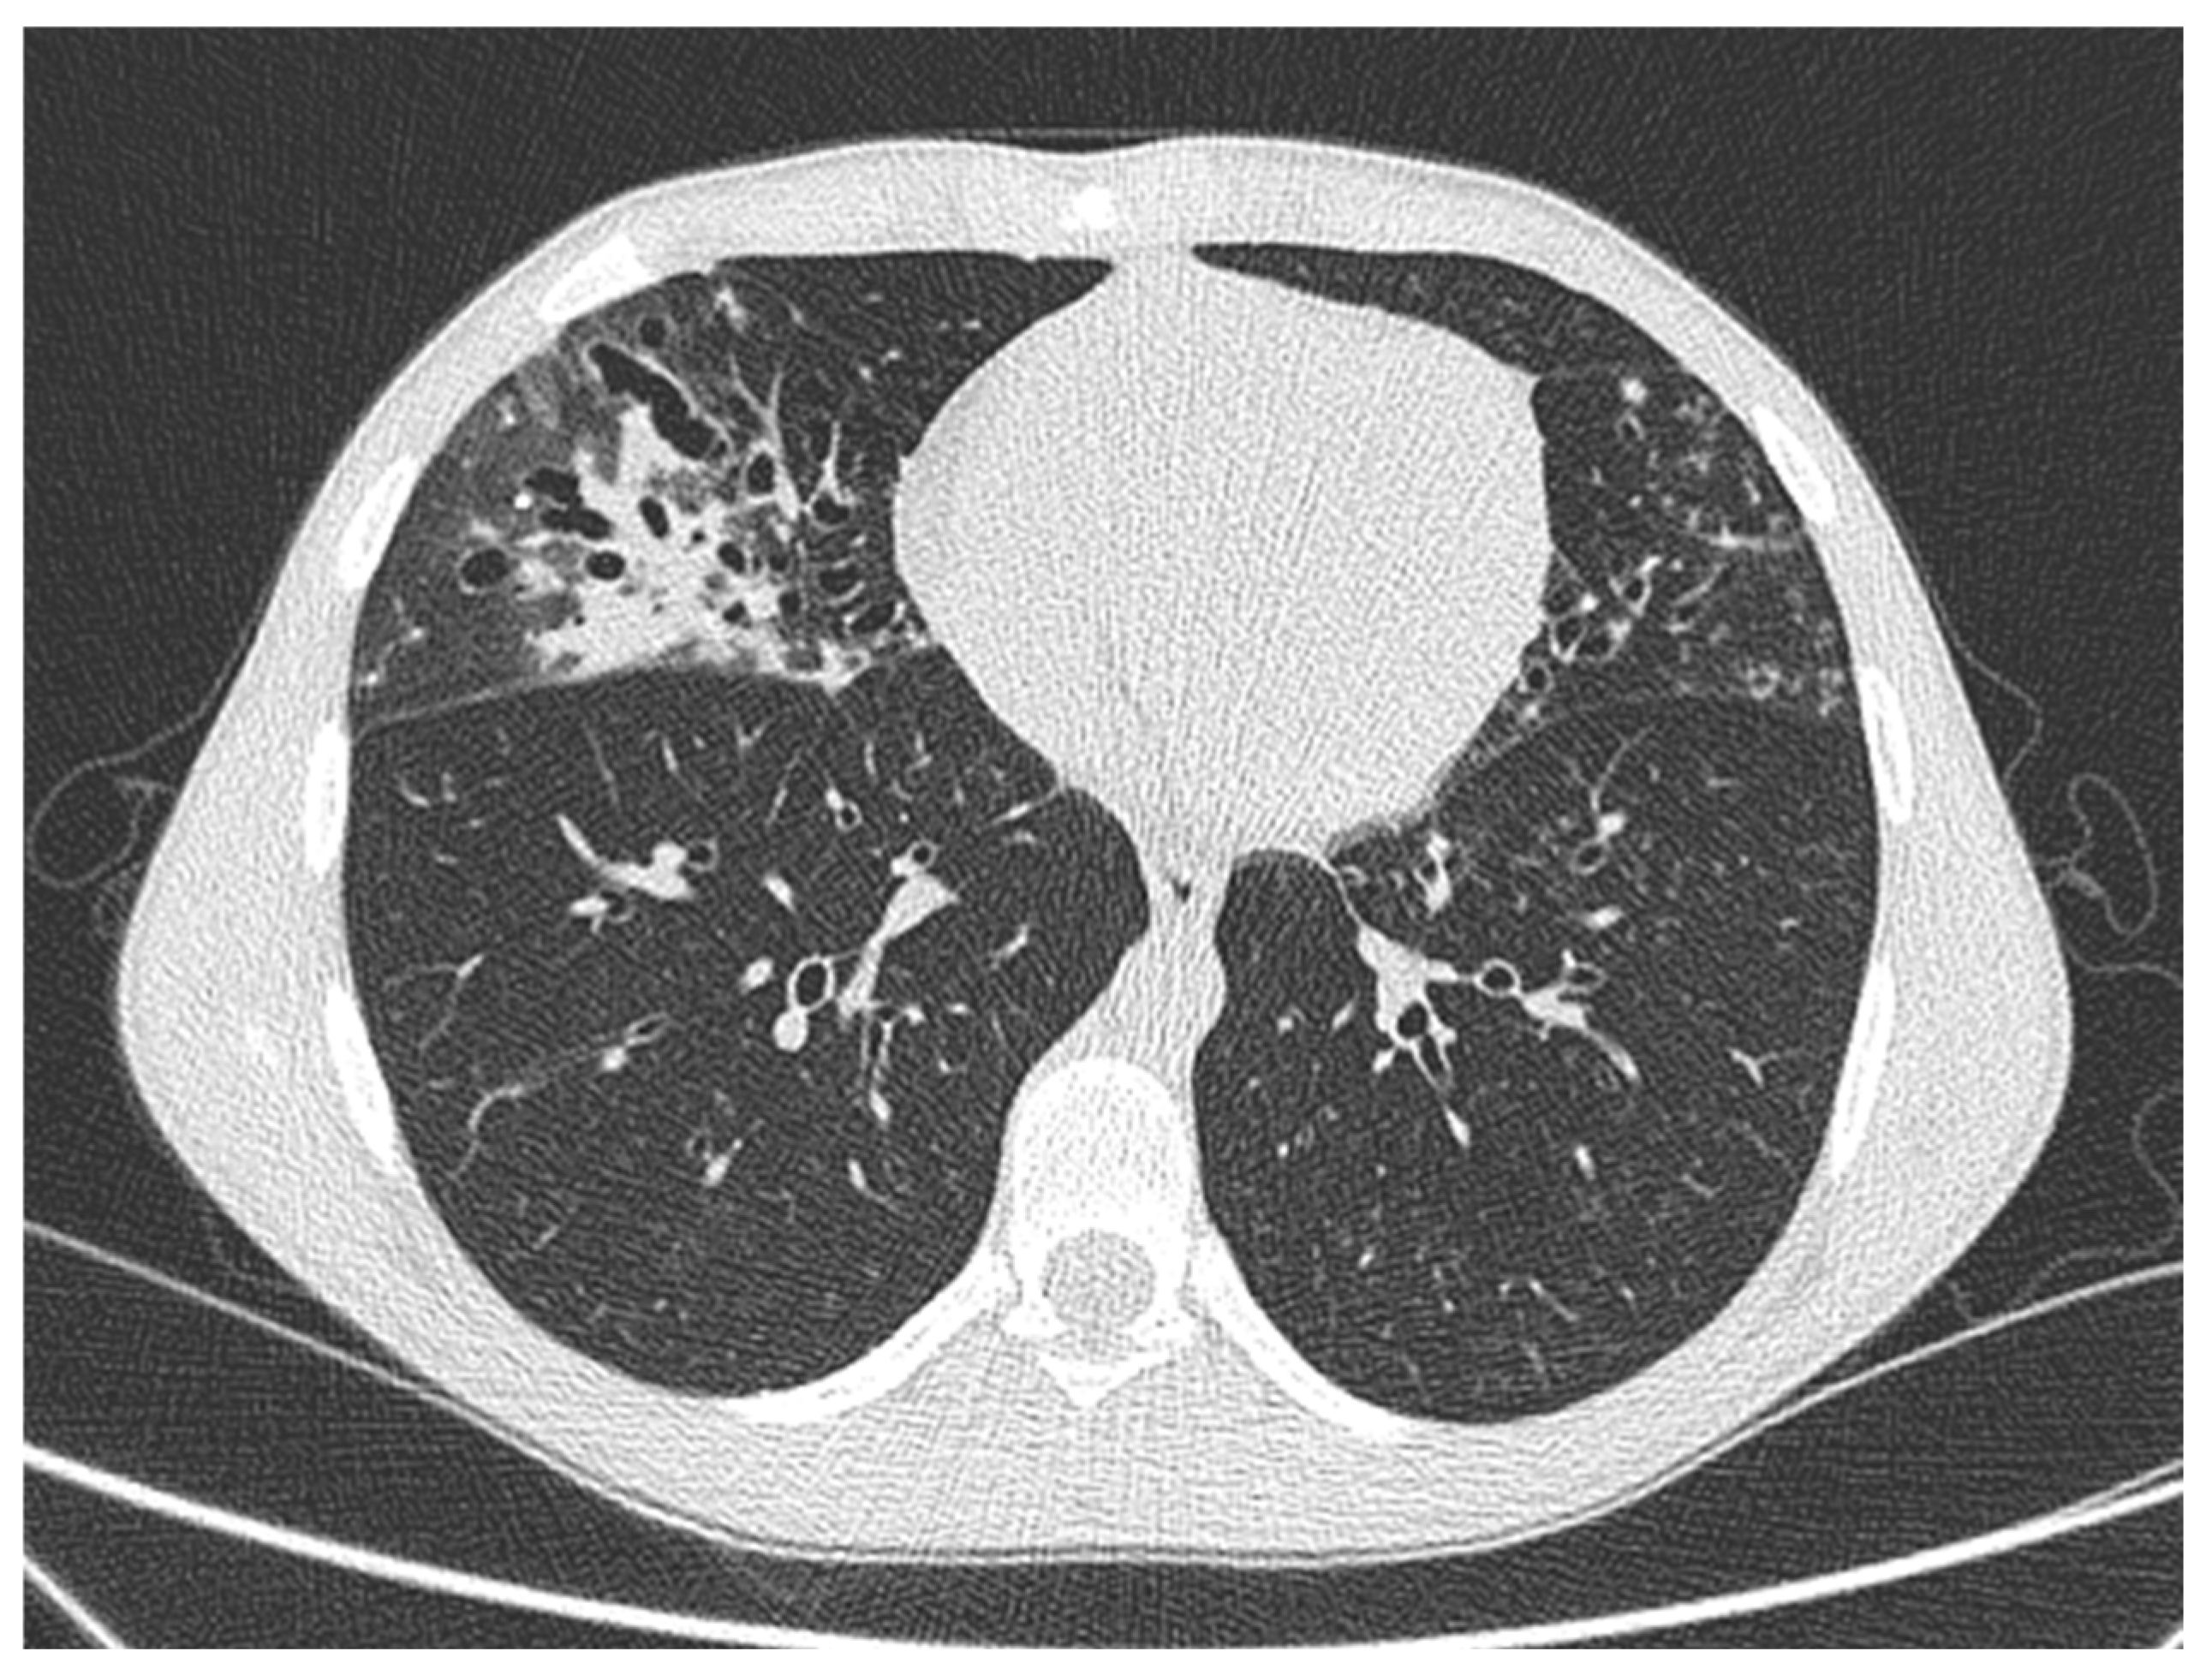

2.1. Case 1

2.2. Case 2

2.3. Case 3

2.4. Case 4

| CE02 | 26 | Klebsiella pneumoniae; Serratia marcescens | Fever, cough | Chest CT: consolidation in known bronchiectasis | 73 | 87 | 23.4 | 25.1 | Amikacin and Cefotaxime (14 days) | Yes |

| VE01 | 18 | Haemophilus spp.; PA | Cough, increased secretions | Chest CT: consolidation and mucous plugs, new tree in bud aspect in the lingula, upper and lower lobe, left lower lobe consolidation. | 94 | 107 | 19.59 | NA | Amikacin and Ceftazidime (14 days) ˜ | No |